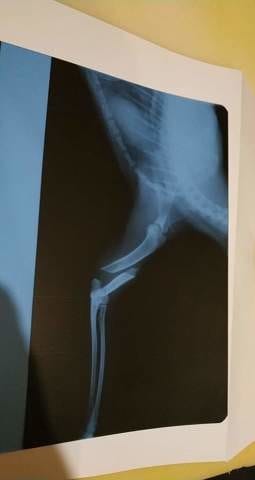

Bonjour a vous voilà mon chat a glisser du rebord de fenêtre de mon appartement (3eme étage) le 31 au soir j'ai appelé plein de véto qui on pas voulu me prendre car je leur et demander si il pouvais me laisser payer en plusieurs fois a partir de lundi .

Et je suis inkiette car je c'est pas si c'est juste casser car il se plain pas de douleur juste quand je le porte de sa patte avant .

Mais au niveau de la clavicule enfaite sa pâte elle pend .

J'aurai voulu savoir si il se peu que se soit juste déboiter